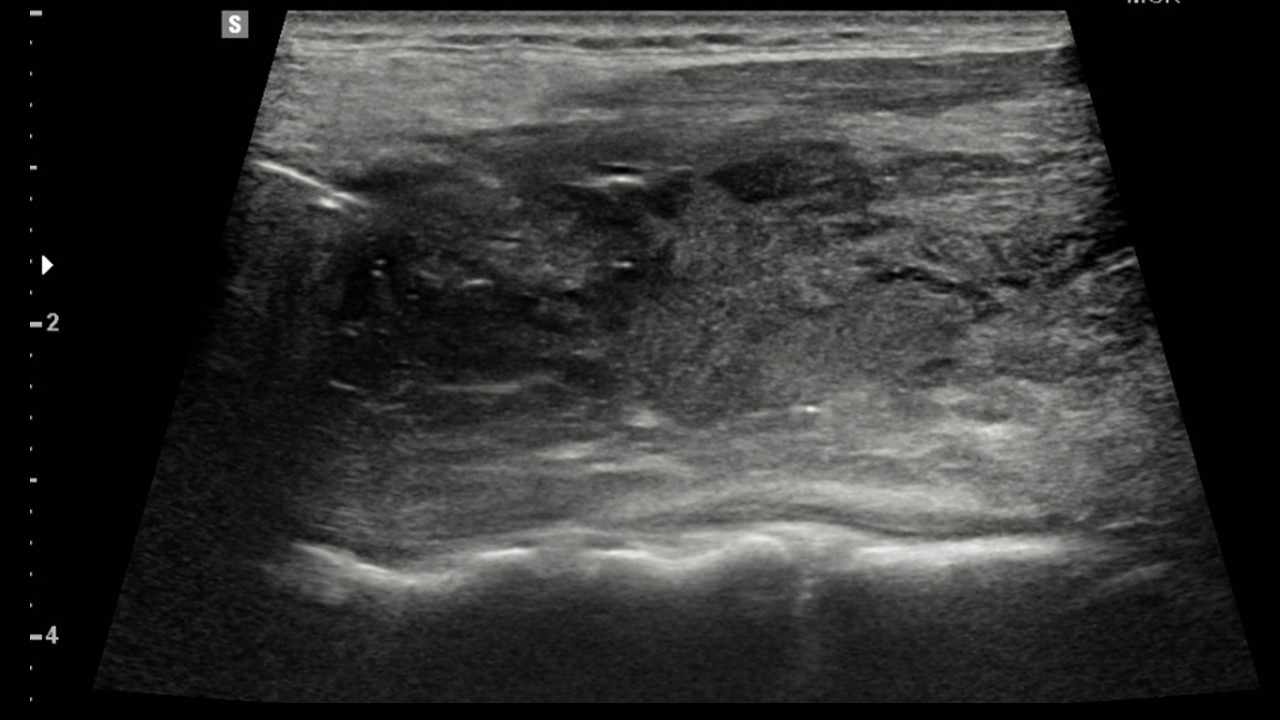

[369,] 48/F,Sore throat, neck pain

Modality

US,CT,

What is the most likely diagnosis?

[Diagnosis]

1.

Hypopharynx cancer with thyroid invasion

2.

Infected 4th branchial cleft anomaly

3.

Infected thyroglossal duct cyst

4.

Anaplastic thyroid cancer

5.

Infected 3rd branchial cleft anomaly